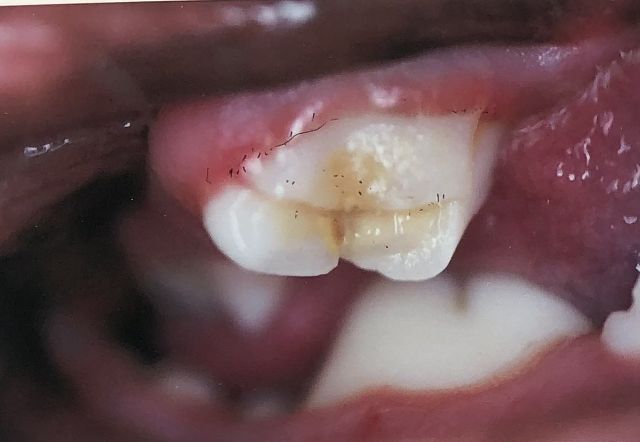

先日、2歳になったばかりの犬があくびをしていた時に、何気なく奥の歯に色が付着しているのが見え、口を開かせてみると、歯に亀裂が入り、しっかりと割れているのを発見しました。 直ぐに獣医に見せたのですが、歯髄まで出ていると痛みがあったり、歯茎が腫れてきたり、そのままにしていると内臓まで悪くする事があると説明され、抜くしか無いのかと思っていたのですが、「ここでは特に何も出来ない」との事! そのまま放っておくのは心配だったので、自分で行けそうな犬の歯医者をネットで探し、その足でもう一度診察してもらいました… が、そこでも4月から抜歯はしていないとの事。 諦めず、抜歯ができる病院を探し、やっと相談することが出来ました。 犬猫歯科に行けば、人間のような歯の治療も出来る子もいるが、ここでの選択肢は・・・@そく抜歯!Aそのまま落ち着いてしまう子もいるので、少し様子を見て、腫れが出たりするようであれば抜歯をする! との事でした。 犬に歯周病は多いが、虫歯にはなりにくいとの事で、少し様子を見ることにしました。 今回、堅いものを食べさせたかたずねられたのですが、普通に市販されているカミカミボーンや、氷くらいの物でも歯を傷めてしまうことを知り、皆さんにも知っていただきたく、投稿しました。 つい、1人でカミカミして遊んでいるので与えてしまっていた私の責任で、可哀想な事をしてしまい、とても反省しています。 このあとも、しっかり体調の変化を見ていきたいと思います。 長文を読んでいただき、ありがとうございました! | ||